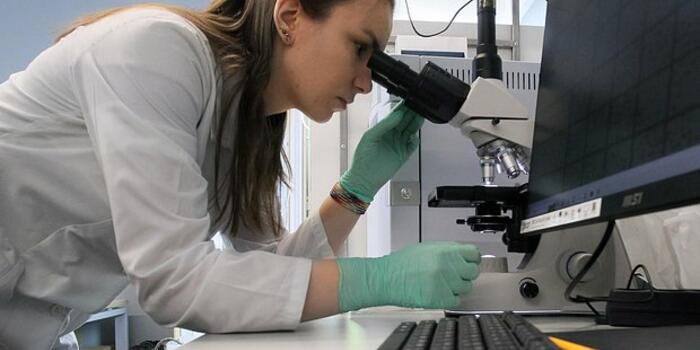

- Xərçəng yoluxucu deyil, amma... [..] - 21 İyun 19:24

Turizm 21 İyun 19:35Xərçəng yoluxucu deyil, amma...

Səhiyyə 21 İyun 19:24Paris fələstinlilərə fəxri vətəndaşlıq verdi...